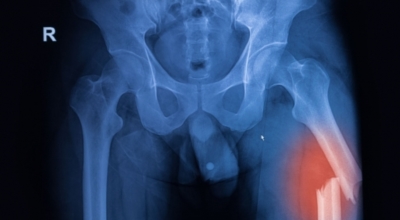

고관절 통증 치료에는 크게 약물 치료와 물리 치료가 있답니다. 고관절염의 진행을 늦추거나 증상을 개선하기 위한 목적으로 항염증제 또는 진통제를 투여해요. 고관절 질환의 일부 증상은 체외 쇼크파, 물리치료, 약물치료 과 같은 비수술 요법으로 증상이 호전될 수 있습니다.

그러나 비수술 치료법으로 개선시키는 것이 어려운 경우 수술적 방법이 고려되어요. 고관절 통증을 조기에 치료하면 약물치료 외에 물리치료로 약 50% 정도 큰 효과를 볼 수 있답니다. 게다가, 보통 고관절 증상 관리에 보탬이 되는 요가, 수영, 스트레칭은 고관절 예방과 치료에 보탬이 돼요.